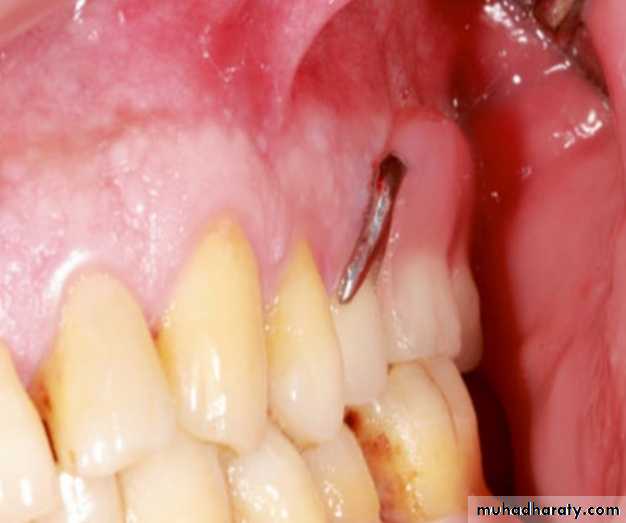

Overextension of the denture bases and the pressures on the fragile tissues such as incisive papilla or occlusal prematurities are the main causes of these ulcerations. Ulcerations due to tissue trauma develop generally at the initial recall appointments and can be solved easily by relieving the denture base parts touching the pain area. In case of overextension, ill-fitting RPDs, or acrylic irregularities, the areas can be identified by the aid of an indelible pencil or pressure- indicating paste. An ulceration due to tissue trauma caused by

the overextension of the lingual border of an RPD

Nevertheless, it is much better to prefer an indelible pencil because using a pressure- indicating paste or cream for determining these areas may cause faulty results as the paste is easily displaced due to its softnessAn indelible pencil may be used to mark the

ulceration area

The indelible pencil is used to mark the ulceration area, and after the area is transferred to the RPD, these parts are

gently removed using a tungsten carbide bur.